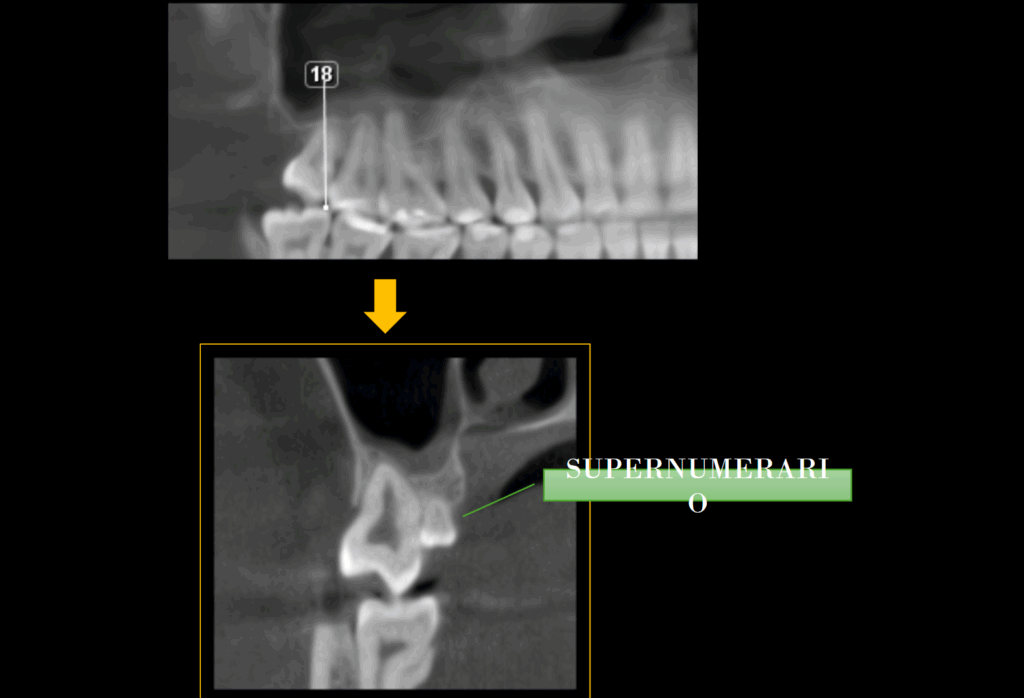

A la evaluación de la tomografía computarizada (en cortes axiales y transaxiales) se puede observar la presencia de una pieza supernumeraria de tamaño reducido (microdiente)localizada por lingual de la pieza 18 y que al evaluar los cortes tangenciales se aprecia una discreta dilaceración hacia distal.

PARÁFRISIS

Los microdientes supernumerarios son una anomalía poco frecuente, generalmente aparecen en el área de los terceros molares, y en algunos casos se asocian a alteraciones eruptivas, apiñamiento o impactación dentaria.

Aunque muchos son asintomáticos y se detectan de manera incidental en estudios radiográficos, otros pueden interferir en la erupción normal o complicar procedimientos quirúrgicos. El diagnóstico preciso requiere radiografías panorámicas o, idealmente, tomografía computarizada de haz cónico (CBCT), que permite evaluar posición tridimensional y relación con estructuras vecinas.

Su manejo depende de la repercusión clínica: pueden observarse si no generan problemas, o ser extraídos cuando comprometen la erupción, o representan riesgo de patología asociada. Reconocer esta variante es clave para la planificación odontológica y quirúrgica.